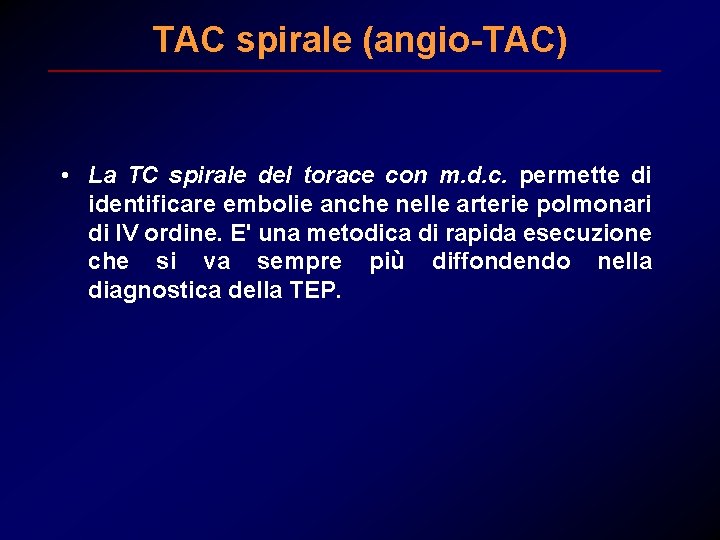

TAC spirale (angio-TAC) • La TC spirale del torace con m. d. c. permette di identificare embolie anche nelle arterie polmonari di IV ordine. E' una metodica di rapida esecuzione che si va sempre più diffondendo nella diagnostica della TEP.